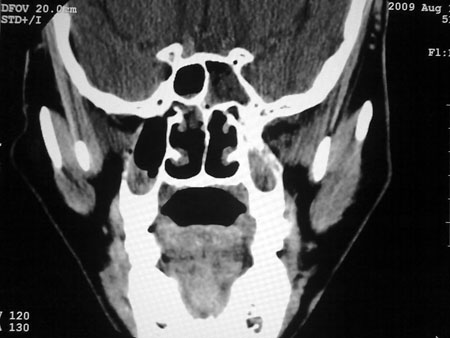

标题: CT21563:M,49,反复鼻塞流脓涕2年余,双侧鼻腔少量水样分 [打印本页]

标题: CT21563:M,49,反复鼻塞流脓涕2年余,双侧鼻腔少量水样分

息肉

双侧鼻息肉,全付鼻窦炎,鼻中隔偏曲。

1)考虑双侧鼻腔及右侧上颌窦息肉。2)全组副鼻窦炎,并左侧额窦粘液囊肿突入左侧眼眶及左侧前颅窝,右侧上颌窦积液。3)鼻中隔偏曲。

(注:上述左右序号可能全反)

双侧鼻息肉,全付鼻窦炎,鼻中隔偏曲;左侧眼眶内上壁可见一类圆形软组织影,占位)建议平扫眼眶

1)考虑双侧鼻腔及右侧上颌窦息肉。2)全组副鼻窦炎,并左侧额窦粘液囊肿突入左侧眼眶及左侧前颅窝,右侧上颌窦积液。3)鼻中隔偏曲。

1)考虑双侧鼻腔及右侧上颌窦息肉。2)全组副鼻窦炎,并左侧额窦粘液囊肿突入左侧眼眶及左侧前颅窝,右侧上颌窦积液。3)鼻中隔偏曲。

1)考虑双侧鼻腔及右侧上颌窦息肉。2)全组副鼻窦炎,并左侧额窦粘液囊肿突入左侧眼眶及左侧前颅窝,右侧上颌窦积液。3)鼻中隔偏曲。

1)考虑双侧鼻腔及右侧上颌窦息肉。2)全组副鼻窦炎,并左侧额窦粘液囊肿突入左侧眼眶及左侧前颅窝,右侧上颌窦积液。3)鼻中隔偏曲。

1)考虑双侧鼻腔及右侧上颌窦息肉。2)全组副鼻窦炎,并左侧额窦粘液囊肿突入左侧眼眶及左侧前颅窝,右侧上颌窦积液。3)鼻中隔偏曲。

1)考虑双侧鼻腔及右侧上颌窦息肉。2)全组副鼻窦炎,并左侧额窦粘液囊肿突入左侧眼眶及左侧前颅窝,右侧上颌窦积液。3)鼻中隔偏曲。

1)考虑双侧鼻腔及右侧上颌窦息肉。2)全组副鼻窦炎,并左侧额窦粘液囊肿突入左侧眼眶及左侧前颅窝,右侧上颌窦积液。3)鼻中隔偏曲。

1)考虑双侧鼻腔及右侧上颌窦息肉。2)全组副鼻窦炎,并左侧额窦粘液囊肿突入左侧眼眶及左侧前颅窝,右侧上颌窦积液。3)鼻中隔偏曲。